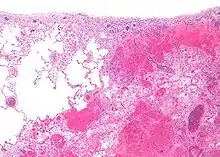

Micrograph of a pulmonary infarct (right of image) beside relatively normal lung (left of image). H&E stain.